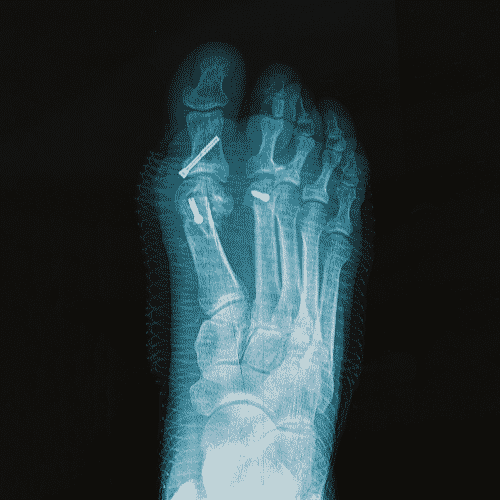

Hallux Valgus (Bunion)

Hallux valgus or bunion is the most common foot deformity. A bunion is a bump that forms on the outside of the big toe. This foot deformity occurs from years of pressure on the big toe joint (the metatarsophalangeal or MTP joint). Eventually, the toe joint gets out of alignment, and a bony bump forms.

Hallux Varus

Hallux varus occurs when the big toe angles away from the second toe. This can cause the big toe to rub against the inside of shoes which makes finding comfortable shoes very difficult. The most common cause of hallux varus is failed bunion surgery.